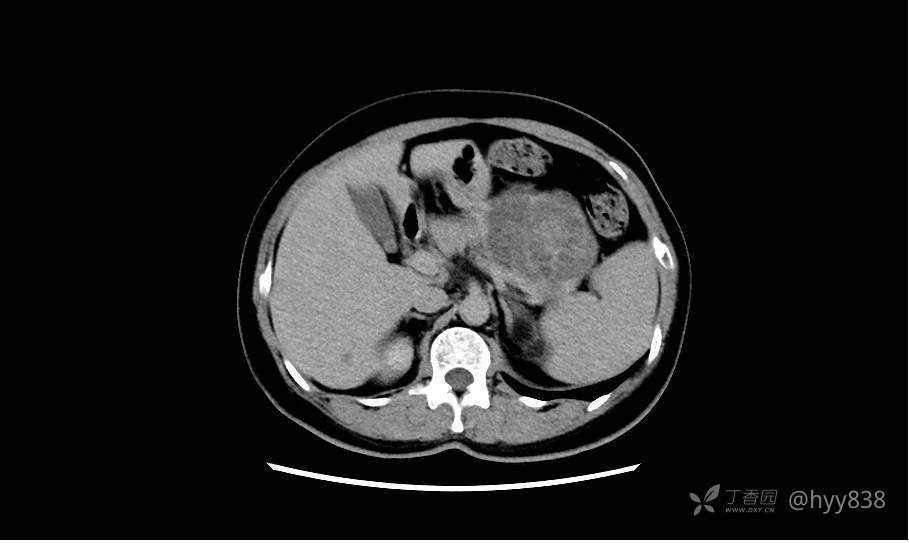

简要病史:2周前,患者无明显诱因出现剑突下不适,以隐痛为主,无明显加重、缓解因素。门诊以胰腺巨大占位收入院进一步诊治。

临床诊断:胰腺占位